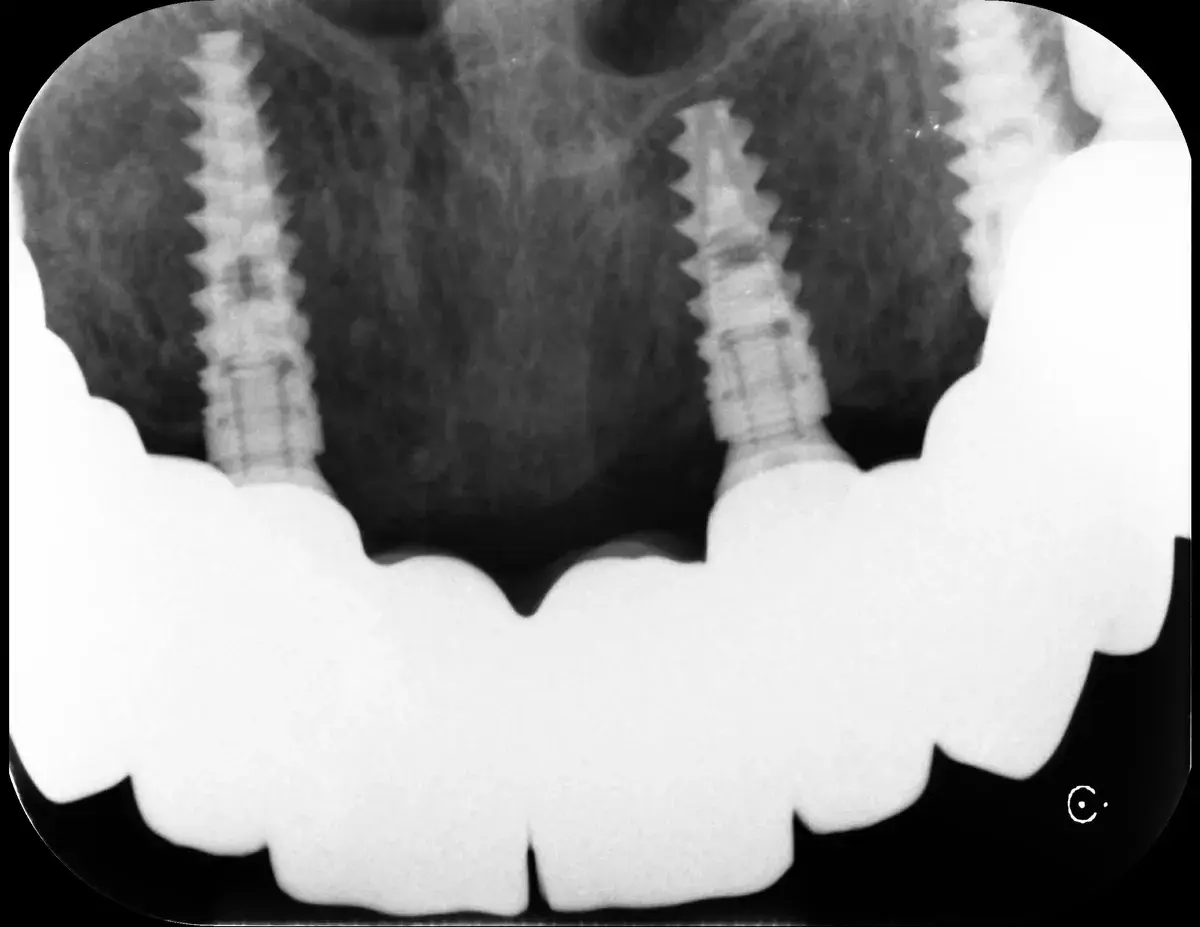

Cresta atrofica in zona 4.6 con difetto osteo-mucoso e cheratinizzata quasi assente: Bonebending 4.0 e impianto in unica seduta. Risultato a 3 mesi.

Caso clinico: espansione crestale ERE con impianto immediato e rigenerazione simultanea. Da ponte fallito a impianto in un'unica seduta.